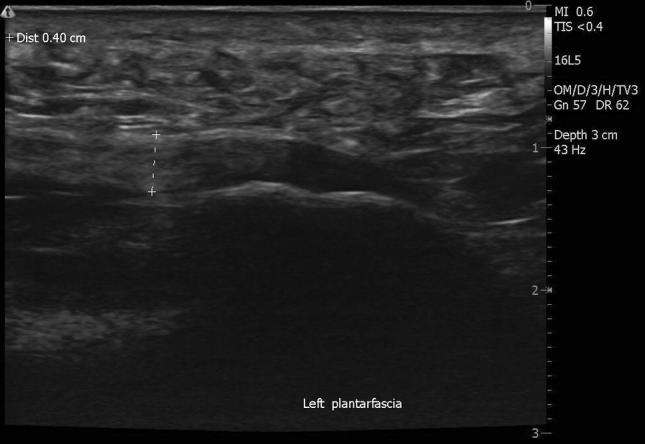

Clinical examination revealed a slight over-pronation of the right foot, the subtalar axis was displaced medially. Mild supination was noted in the left foot, with the subtalar axis slightly lateralized. Radiographs of the bilateral feet were normal. MRI of the foot demonstrated a small effusion in the left peroneus longus and tibialis posterior tendon sheaths. Ultrasound examination revealed non-homogeneous echogenicity in both plantar fasciae, compatible signs of fascial degeneration, and hypoechogenicity on both fascial insertions, but more prominent on the left side, that suggested a chronic plantar fasciosis, Figs. 1 and 2. Both plantar fascia thickness were considered within average values.

Fig. 2.

Ultrasound image of pretreatment of left foot plantar fascia